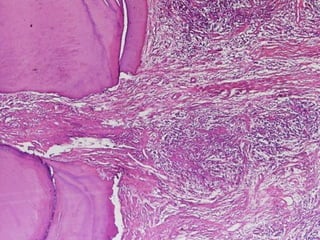

Chronic Hyperplastic Pulpitis

Pulp Polyp

 Histopathological

Features:

 The

polyp consists of granulation tissue.

It contains delicate connective tissue, fibers

and blood vessels.

Mononuclear inflammatory cell infiltration.

The polyp is covered with SS epithelium.